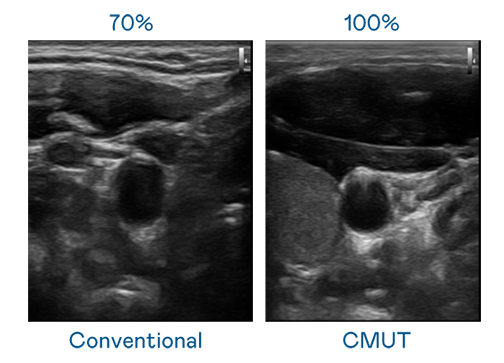

CMUT 技术是一种用电容式微机电元件来产生超音波讯号的技术。与传统 PZT 压电式技术相比,CMUT 频宽增加 30%,更宽频的超音波讯号让影像解析度大幅提升,是实现高影像品质医疗超音波扫描、促进精准医疗发展的关键技术。

超音波影像的解析度高低,首先取决于探头能发出的讯号频宽。意大利贵宾会 CMUT 可提供高清晰的超音波讯号,提供高频宽、高灵敏度、影像纹理细节更高的超音波影像,协助医护人员缩短影像判读时间及利用精准的医疗影像进行诊断。